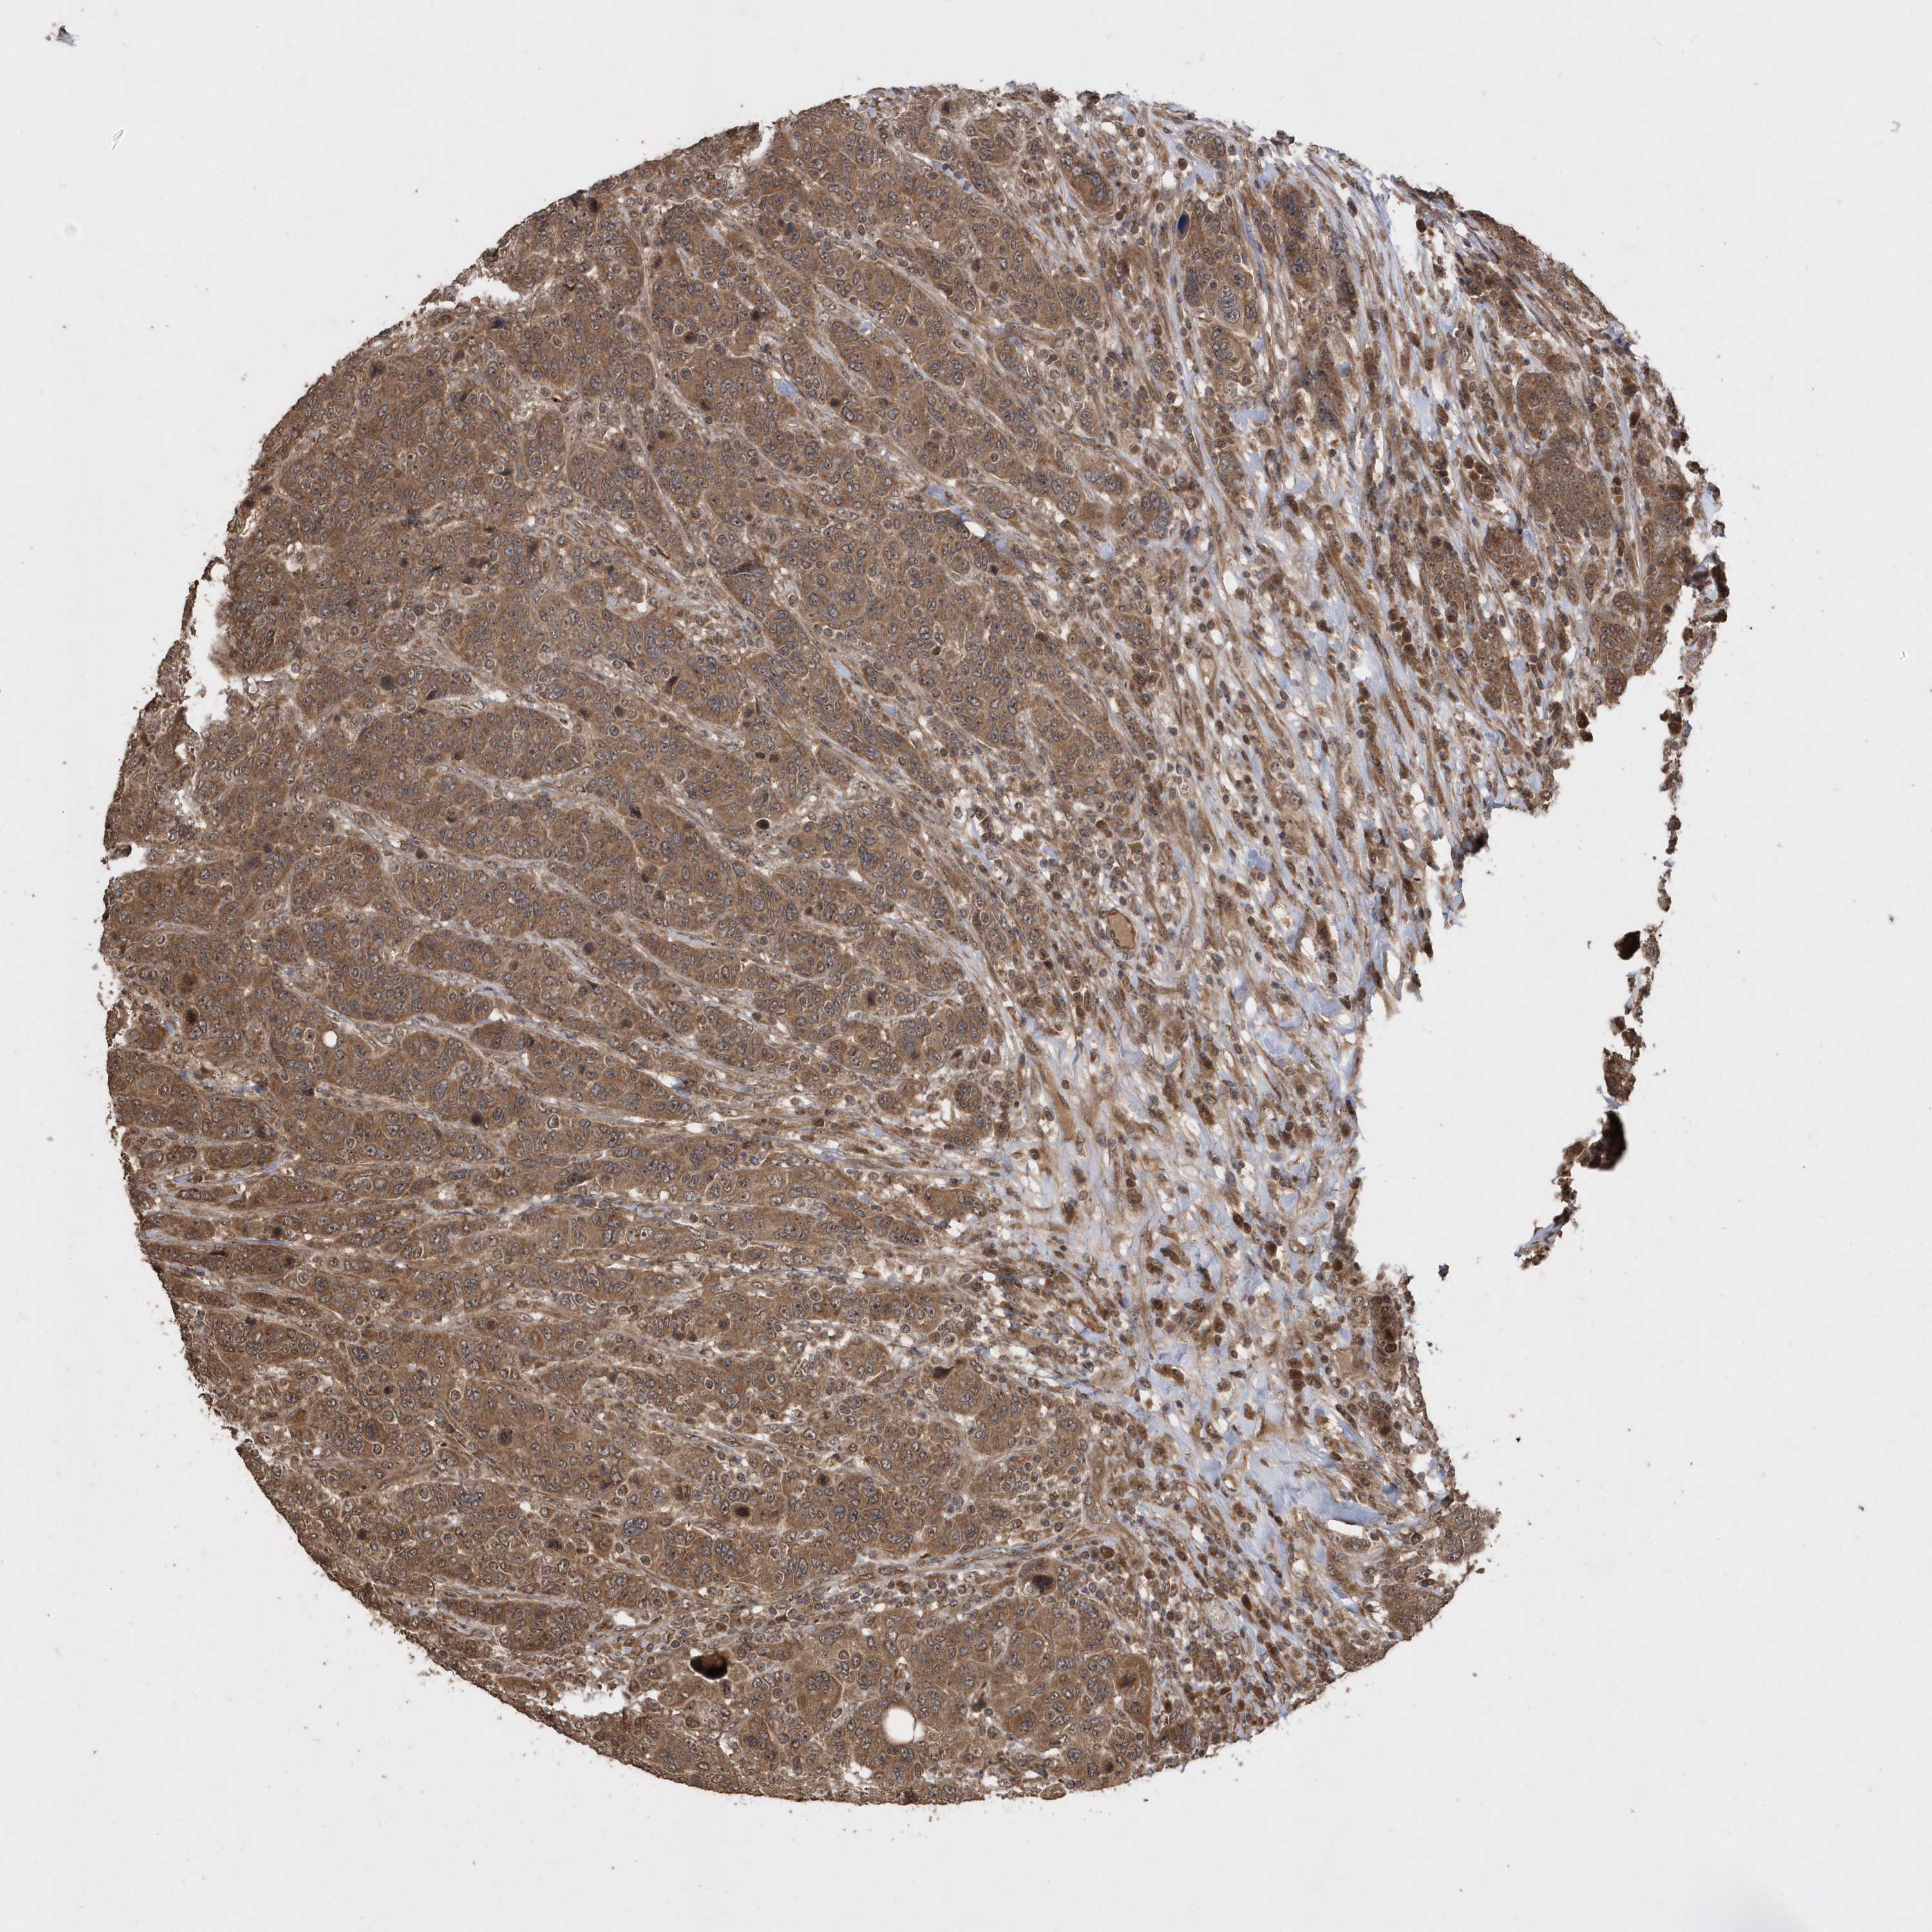

CANCER BREAST CANCER Show tissue menu

BRCA TCGA BRCA VALIDATION PROTEIN EXPRESSION